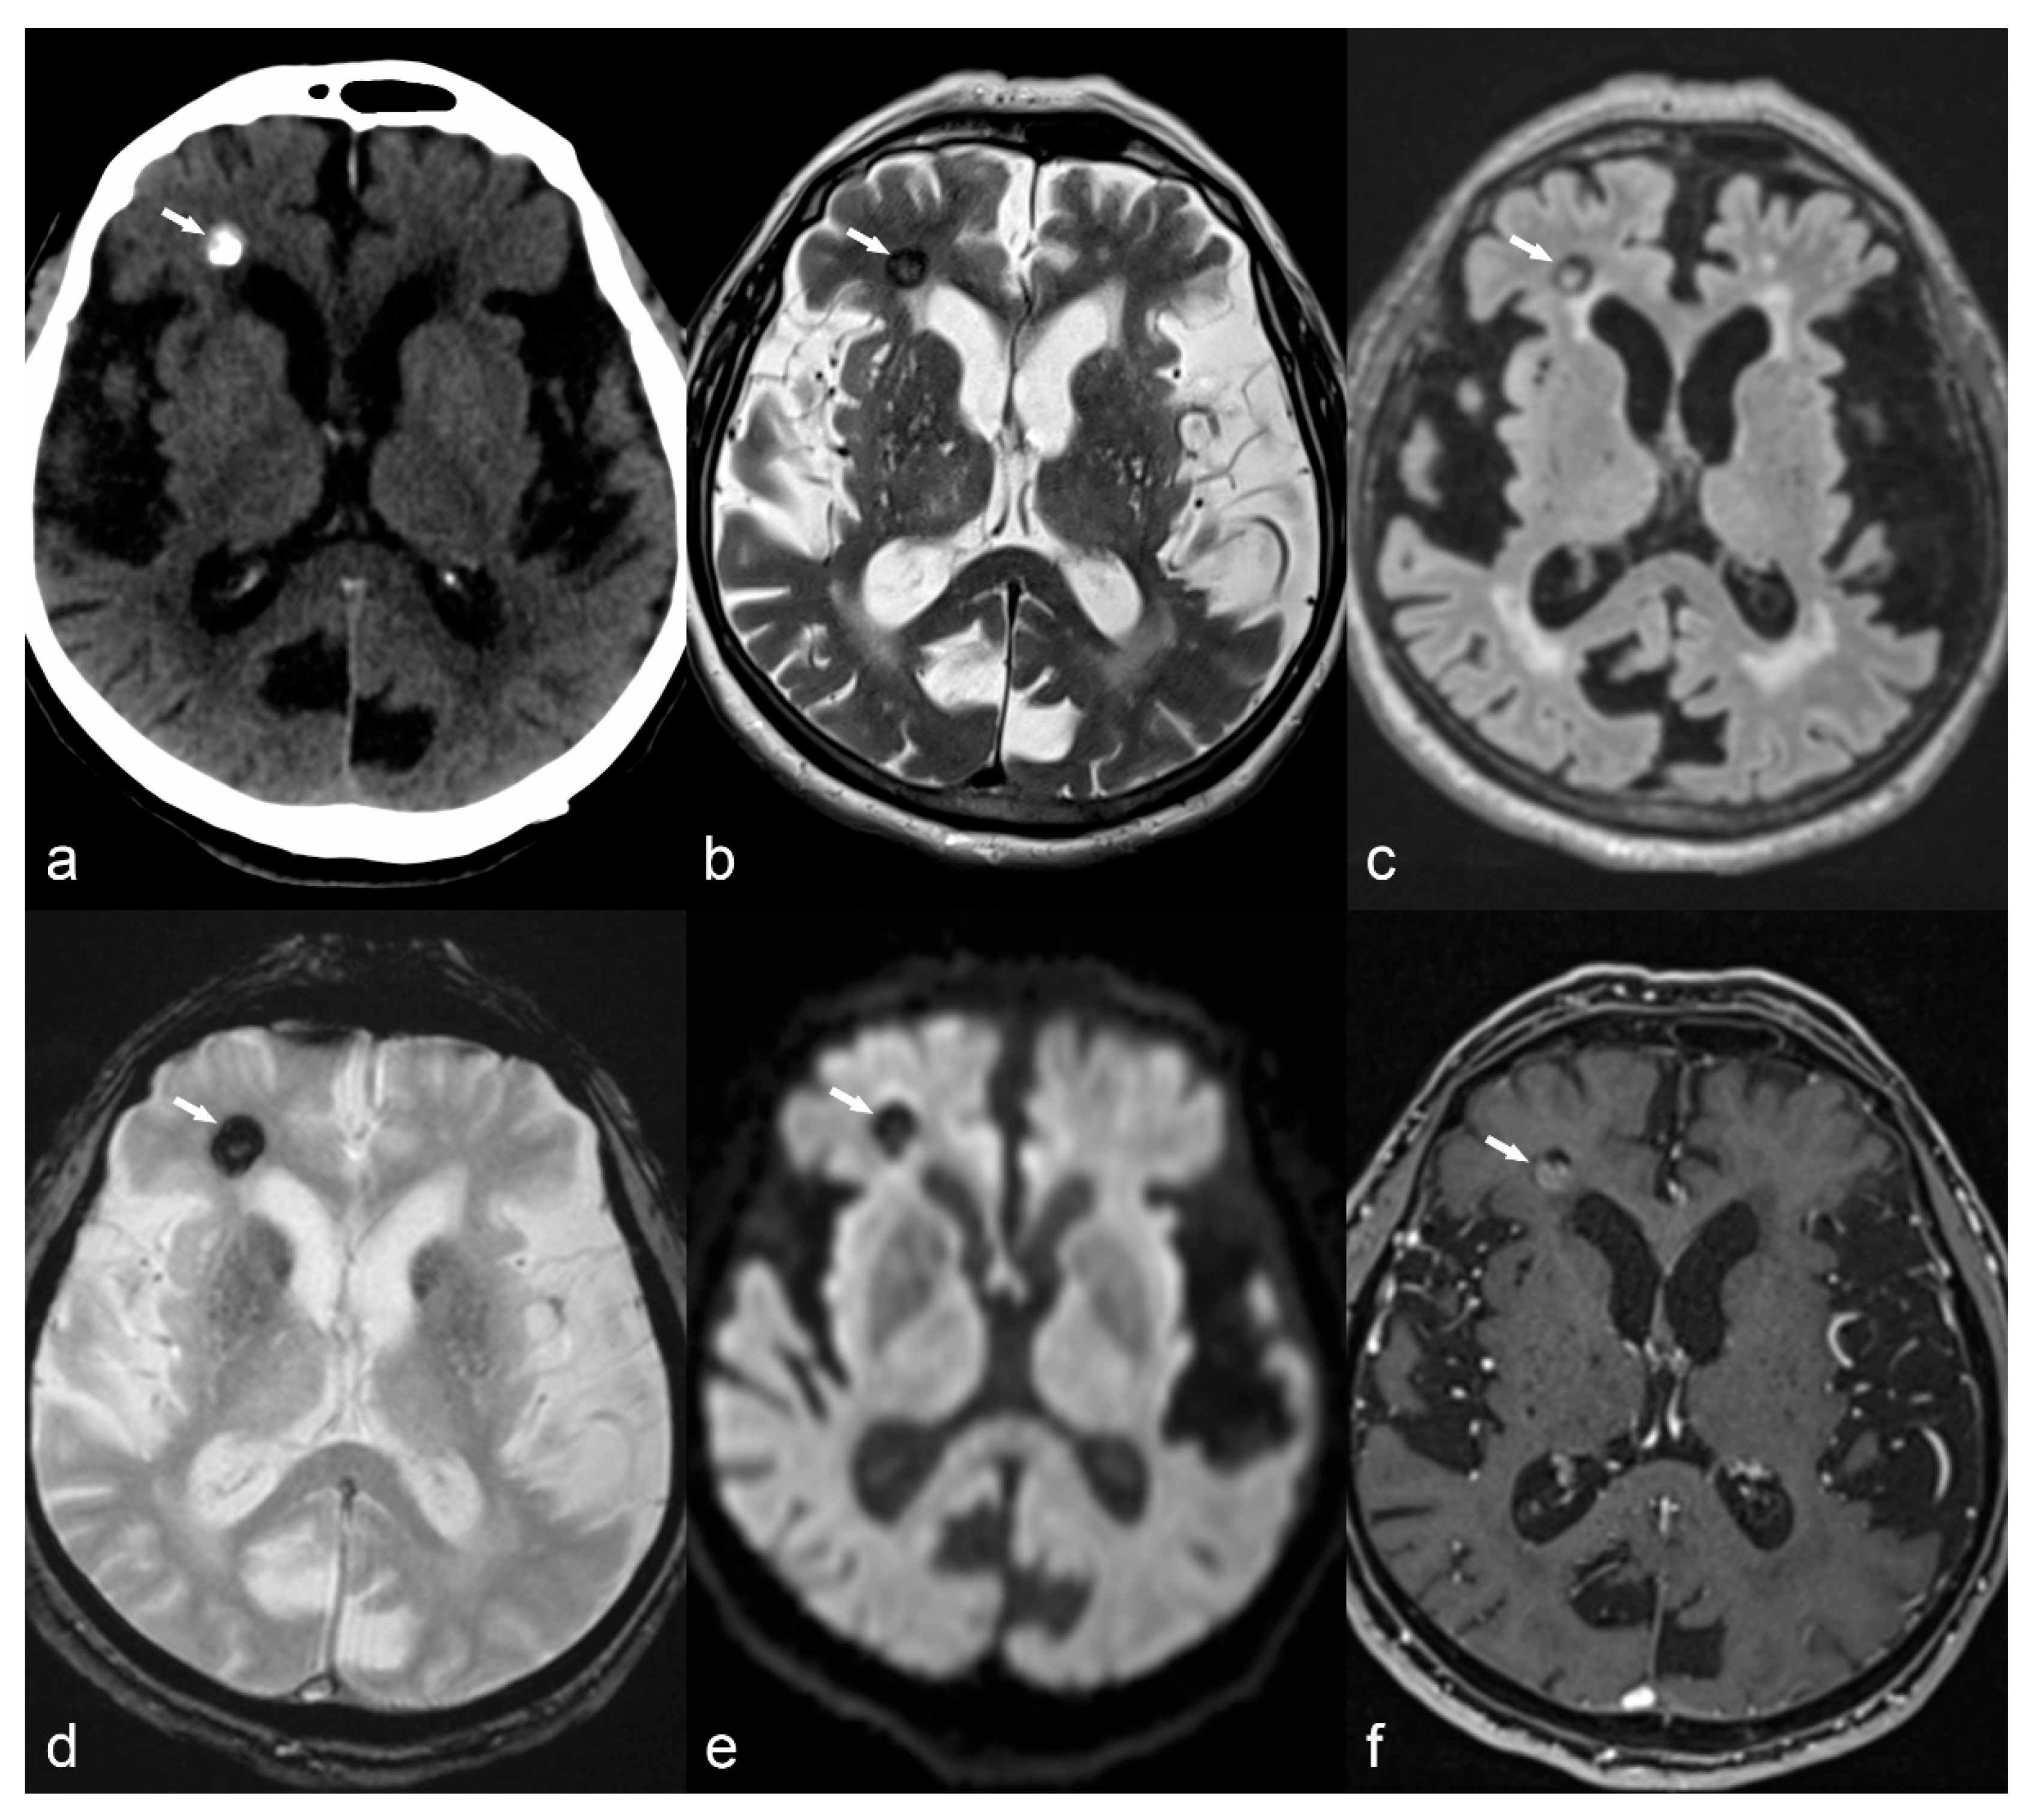

Figure 5.

10-year-old girl with cortical dysplasia. There is thickening of the cortex on the left mesial fronto-parietal region (arrows in (a) to (f)) associated to funnel-shaped hyperintensity of the surrounding white matter (arrows in (b,e)). Note blurring between the white and gray matter interface (f).

Focal cortical dysplasia (FCD) is probably the most common cause of refractory extratemporal focal epilepsy, especially in the pediatric population [75]. Epilepsy due to FCD commonly begins in the first few years of life and may occur shortly after birth [75]. The term “focal cortical dysplasia” was introduced by Taylor et al. [76] in order to describe a malformation of cortical development in the human brain that consisted of disorganized cortex with enlarged dysplastic neurons and enlarged balloon cells. This type of FCD is nowadays classified as FCD type II; type I FCD is also characterized by abnormal cortex with distorted architecture, but individual neurons are normal and not enlarged as in type II [77]. A type III FCD has recently been described, but it is not generally considered a distinct entity in itself; it is FCD I or II associated with another primary lesion, such as HS, tumor, vascular malformation, ischemic scars, or other [78]. FCD type II is characterized by focal cortical thickening, “blurring” of gray/white matter interface, subcortical T2/FLAIR hyperintensity and sometimes a funnel-shaped high T2/FLAIR signal pointing towards the ventricles (“transmantle sign”) (Figure 5) [76,77,78], while findings in FCD type I are usually subtler and this latter is usually more difficult to detect. FCD has a predilection for the frontal lobes, contrary to HS and epileptogenic tumors, usually located in the temporal lobes. FCD represents a great part of “nonlesional” MRIs in patients with medically refractory epilepsy, due to its small size or subtle architectural changes, undetected by neuroimaging techniques. For this reason, multiplanar reconstruction of high-resolution images, as well as advanced methods such as DTI and spectroscopy are important for detection and confirmation of subtle lesions, especially when these are located at the bottom of the sulcus. DTI shows decreased connectivity in the area around the dysplastic cortex and spectroscopy shows decreased NAA/Cr ratio. These techniques or metabolic imaging (PET-CT and SPECT imaging) may highlight suspicious cortical areas, that can be re-inspected on initial MR images [23,79] and increase lesion detection this way. Complete resection of FCD is the best predictor for seizure control [23,42] and for this reason surgical treatment has better outcomes for FCD type II compared to type I. Presurgical detection of the epileptogenic focus is therefore of the utmost importance. Close correlation of semiology, EEG, MRI with advanced techniques and/or ultra-high field, as well as PET-CT/SPECT findings, is required in order to improve prognosis not only for seizure control of these patients, but also for the developmental outcome in the pediatric population suffering from epilepsy due to FCD treated by surgery at early stages [23,80,81].